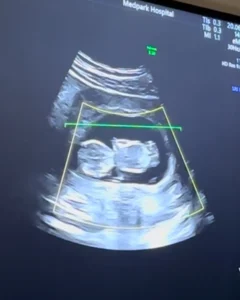

ก่อนหน้านี้ทางด้านนักร้องสาวชื่อดัง แพท วงเคลียร์ ได้มีการออกมาประกาศข่าวดีว่ากำลังตั้งครรภ์ลูกคนแรกสร้างความดีใจให้กับแฟนคลับแฟนเพลงเป็นอย่างมาก

โดยล่าสุดเจ้าตัวได้ออกมาอัพเดทภาพขณะที่ใส่ชุดเดรสบอกเลยว่าคุณแม่ยังคงสวยเหมือนเดิมเลยทีเดียวจ้าเอาเป็นว่าเราไปชมภาพล่าสุดกันได้เลย